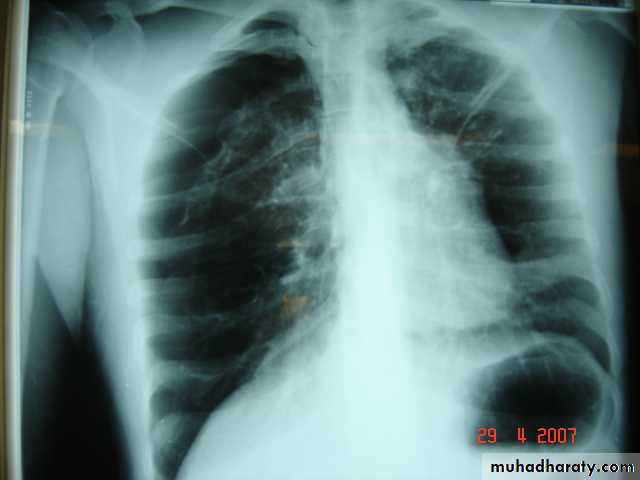

• Radiological Findings

• 1-Smooth homogenous opacity (Intact H.C).• 2-Partial rupture (per vesicular pneumocyst).

• 3-Complete rupture (Water –lilly sign) .

• 4-Formation of lung abscess(Air –fluid level) .

• 5-Completely coughed out cyst(empty cavity )

• 6-Rupture into the pleura (hydropneumothorax)